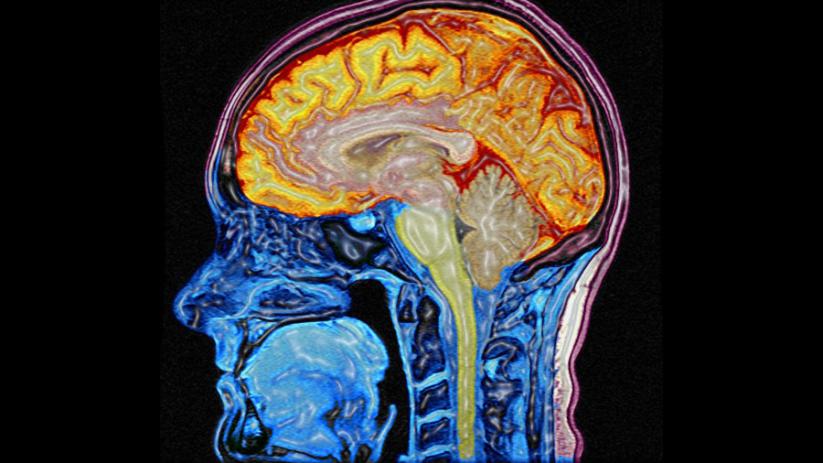

DHA is required for the formation of myelin, the white matter that insulates our brain circuits, allowing electricity to flow through them and our nervous system to function properly.

"Perhaps most importantly, DHA is critical to the development of the human cortex-the part of the brain responsible for higher-order thinking," writes Harvard-trained psychiatrist Georgia Ede in a Psychology Today article titled The Brain Needs Animal Fat.

"Without DHA, the highly sophisticated connections necessary for sustained attention, decision-making, and complex problem-solving do not form properly. It has been hypothesized that without DHA, consciousness and symbolic thinking-hallmarks of the human race-would be impossible.”